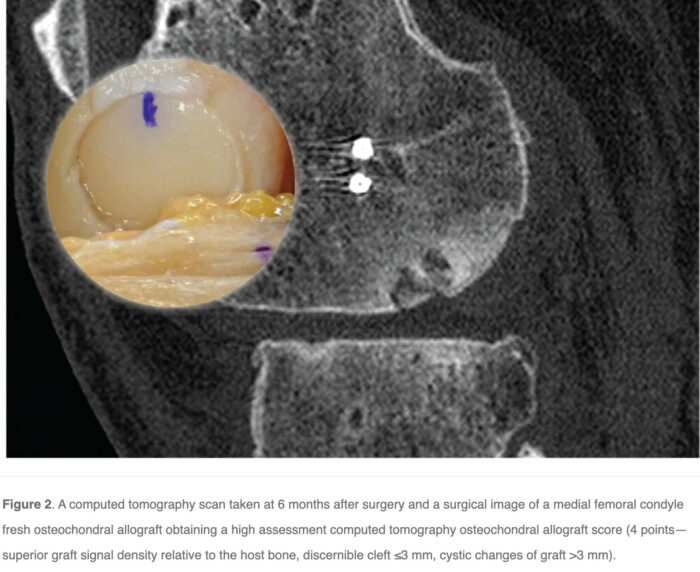

Questions: How effective is computed tomography (CT) scans in predicting the clinical outcome of fresh osteochondral allograft (FOCA) transplantation using the assessment computed tomography osteochondral allograft (ACTOCA) score?

Methods: All patients were followed up for a minimum of 2 years. CT scans performed 6 months after surgery were evaluated by a musculoskeletal radiologist using the ACTOCA scoring system. The radiologist was blinded to the patient’s medical history. Clinical outcomes were assessed preoperatively and at 12 and 30 months postoperatively using the International Knee Documentation Committee (IKDC) score, the Kujala score, the Tegner activity scale, and the Western Ontario Meniscal Evaluation Tool (WOMET) score.

Main Results: The ACTOCA score at 6 months after surgery showed a statistically significant correlation with clinical results at 12 and 30 months. The correlation was better at 30 months, showing a high negative correlation with the IKDC score (−0.663) and a moderate negative correlation with the Kujala, WOMET, and Tegner scores (−0.593; −0.547, and −0.593, respectively) (P < .001).

Conclusion: A statistically significant correlation between the mean ACTOCA score on CT scans at 6 months and the clinical results measured by the IKDC, Kujala, WOMET, and Tegner scores at 30 months confirmed the predictive value of the ACTOCA score for use in clinical practice.

Teaching points: This is an excellent study demonstrating the utility of CT in evaluating the osteochondral transplant fragment incorporation in the native bone. It is often difficult to evaluate the transplanted fragment even on MRI, so the parameters used in this study might be useful in the future.